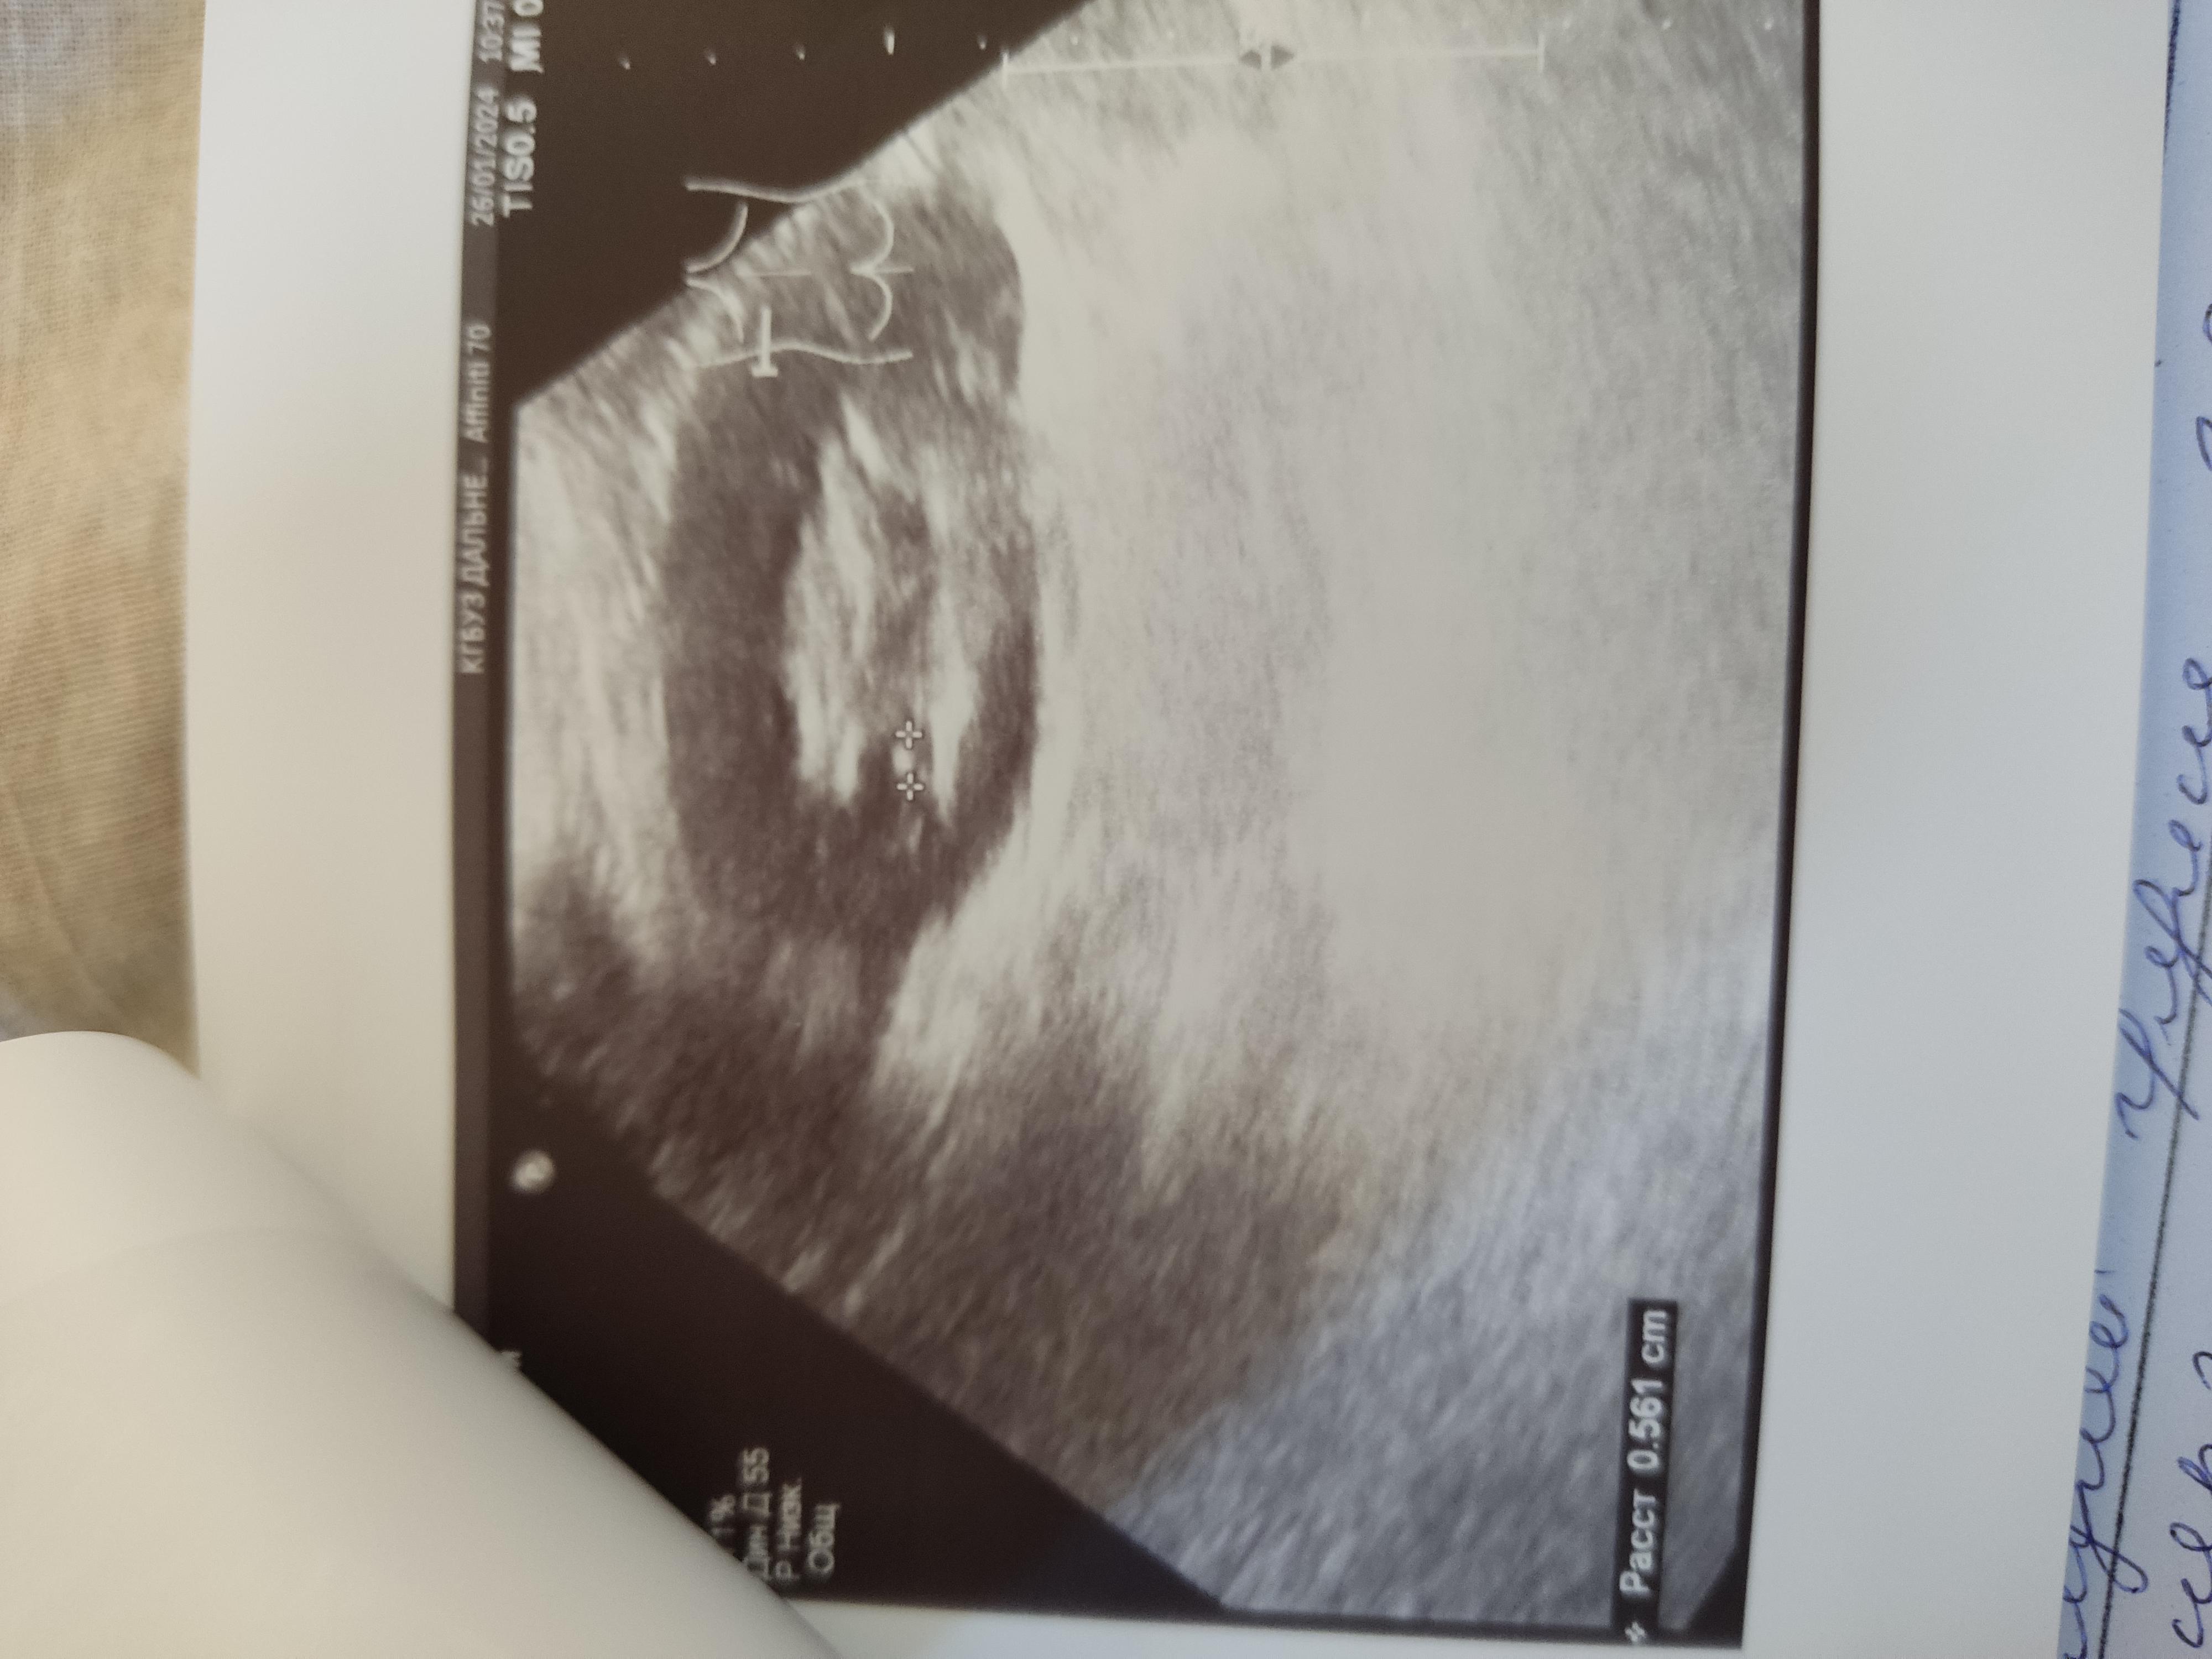

Дд. Помогите расшифровать УЗИ. Камень в почке, ужасные боли. Что можно сделать, чтоб облегчить их и ускорить выход камня? И выйдет ли каиень такого размера? Спасибо

Вам нужно начать с визита к врачу урологу на очный прием. Пройти обследование. Возможно потребуется выполнение компьютерной томографии для точной диагностики и точного выявления локализации камня и его размера. Без обследования, в первую очередь компьютерной томографии, принять решение о возможности или невозможности самостоятельного отхождения камня невозможно.